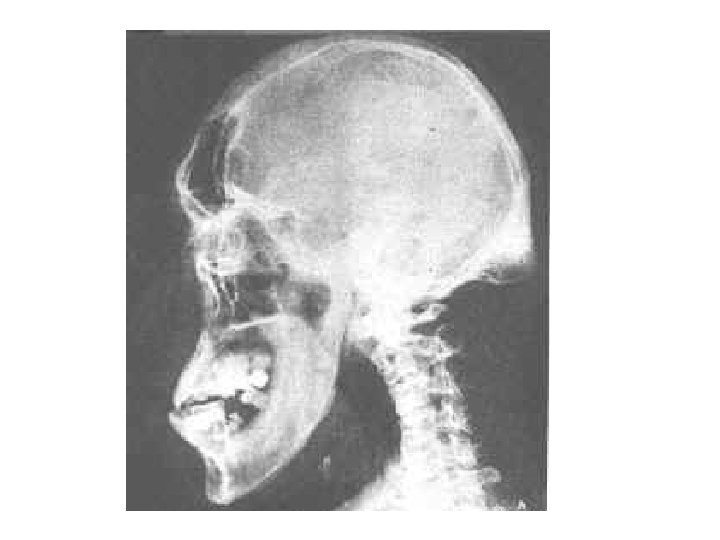

Acromegaly • Acromegaly is a serious condition that occurs when the body produces too much of the hormones that control growth. ・The hormone most often affected is called growth hormone, or GH. It is produced by the pituitary gland, a tiny organ at the base of the brain. ・・ Growth hormone promotes growth of bone, cartilage, muscle, organs, and other tissues. ・・When there is too much growth hormone in the body, these tissues grow larger than normal. This excessive growth can cause serious disease and even premature death.